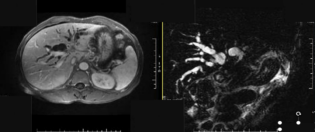

(2)腺癌CT表现:胰腺局部增大、肿块形成,多呈等或稍低密度,增强扫描多呈低密度而显示更清楚;胰头Ca常伴胰体尾萎缩;胰腺钩突变为隆凸或球形,提示钩突肿瘤;胰管和胆管扩张。

胰腺癌MRI表现:横断面所见与CT相同。T1WI肿瘤呈低或等信号,T2WI肿瘤呈稍高信号;MRCP能清晰显示梗阻扩张的胰管和胆管。